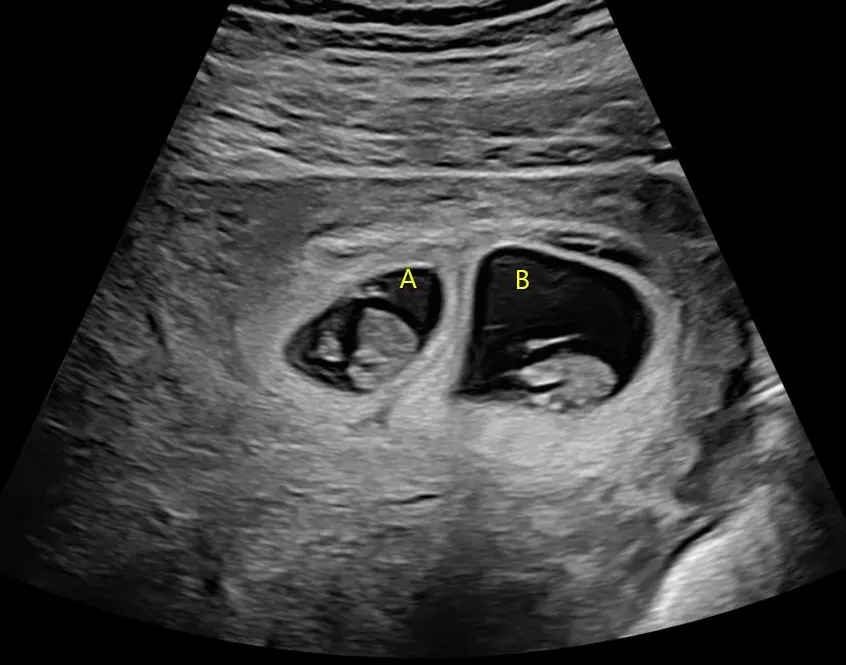

The days of considering the 12 week ultrasound as just a screening test for chromosome abnormalities (like Down syndrome) are long gone. Advances in ultrasound technology mean that we can start to examine your baby’s anatomy much sooner than in the past. The first trimester anatomy scan is performed between 12 and 14 weeks gestation and is an important option to check the development of your baby no matter your choices for chromosomal screening.

During this ultrasound we will check your baby’s heart beat, growth as well as the due date for your pregnancy. Our dedicated team will also check:

- Anatomy of your baby

- Nuchal Translucency

- Placental location and ovaries

With advances in ultrasound technology, your baby’s anatomy can be seen in great detail between 12 and 14 weeks gestation. It is now possible to see your baby’s arms, legs, fingers, and toes as well as skull, heart, brain, stomach, and kidneys.

During this ultrasound we undertake additional tests to screen your baby (if requested) for you, your cervical length, and risks of developing pre-eclampsia. This involves:

- Chromosomal anomalies by measuring the nuchal translucency thickness

- Risk of pre-eclampsia by measuring the uterine artery blood flow

- Assess for pre-term birth through measuring the length of the cervix

Whether you choose to have screening for chromosomal abnormalities or not, the 1st trimester anatomy scan can provide much more information on your growing baby.